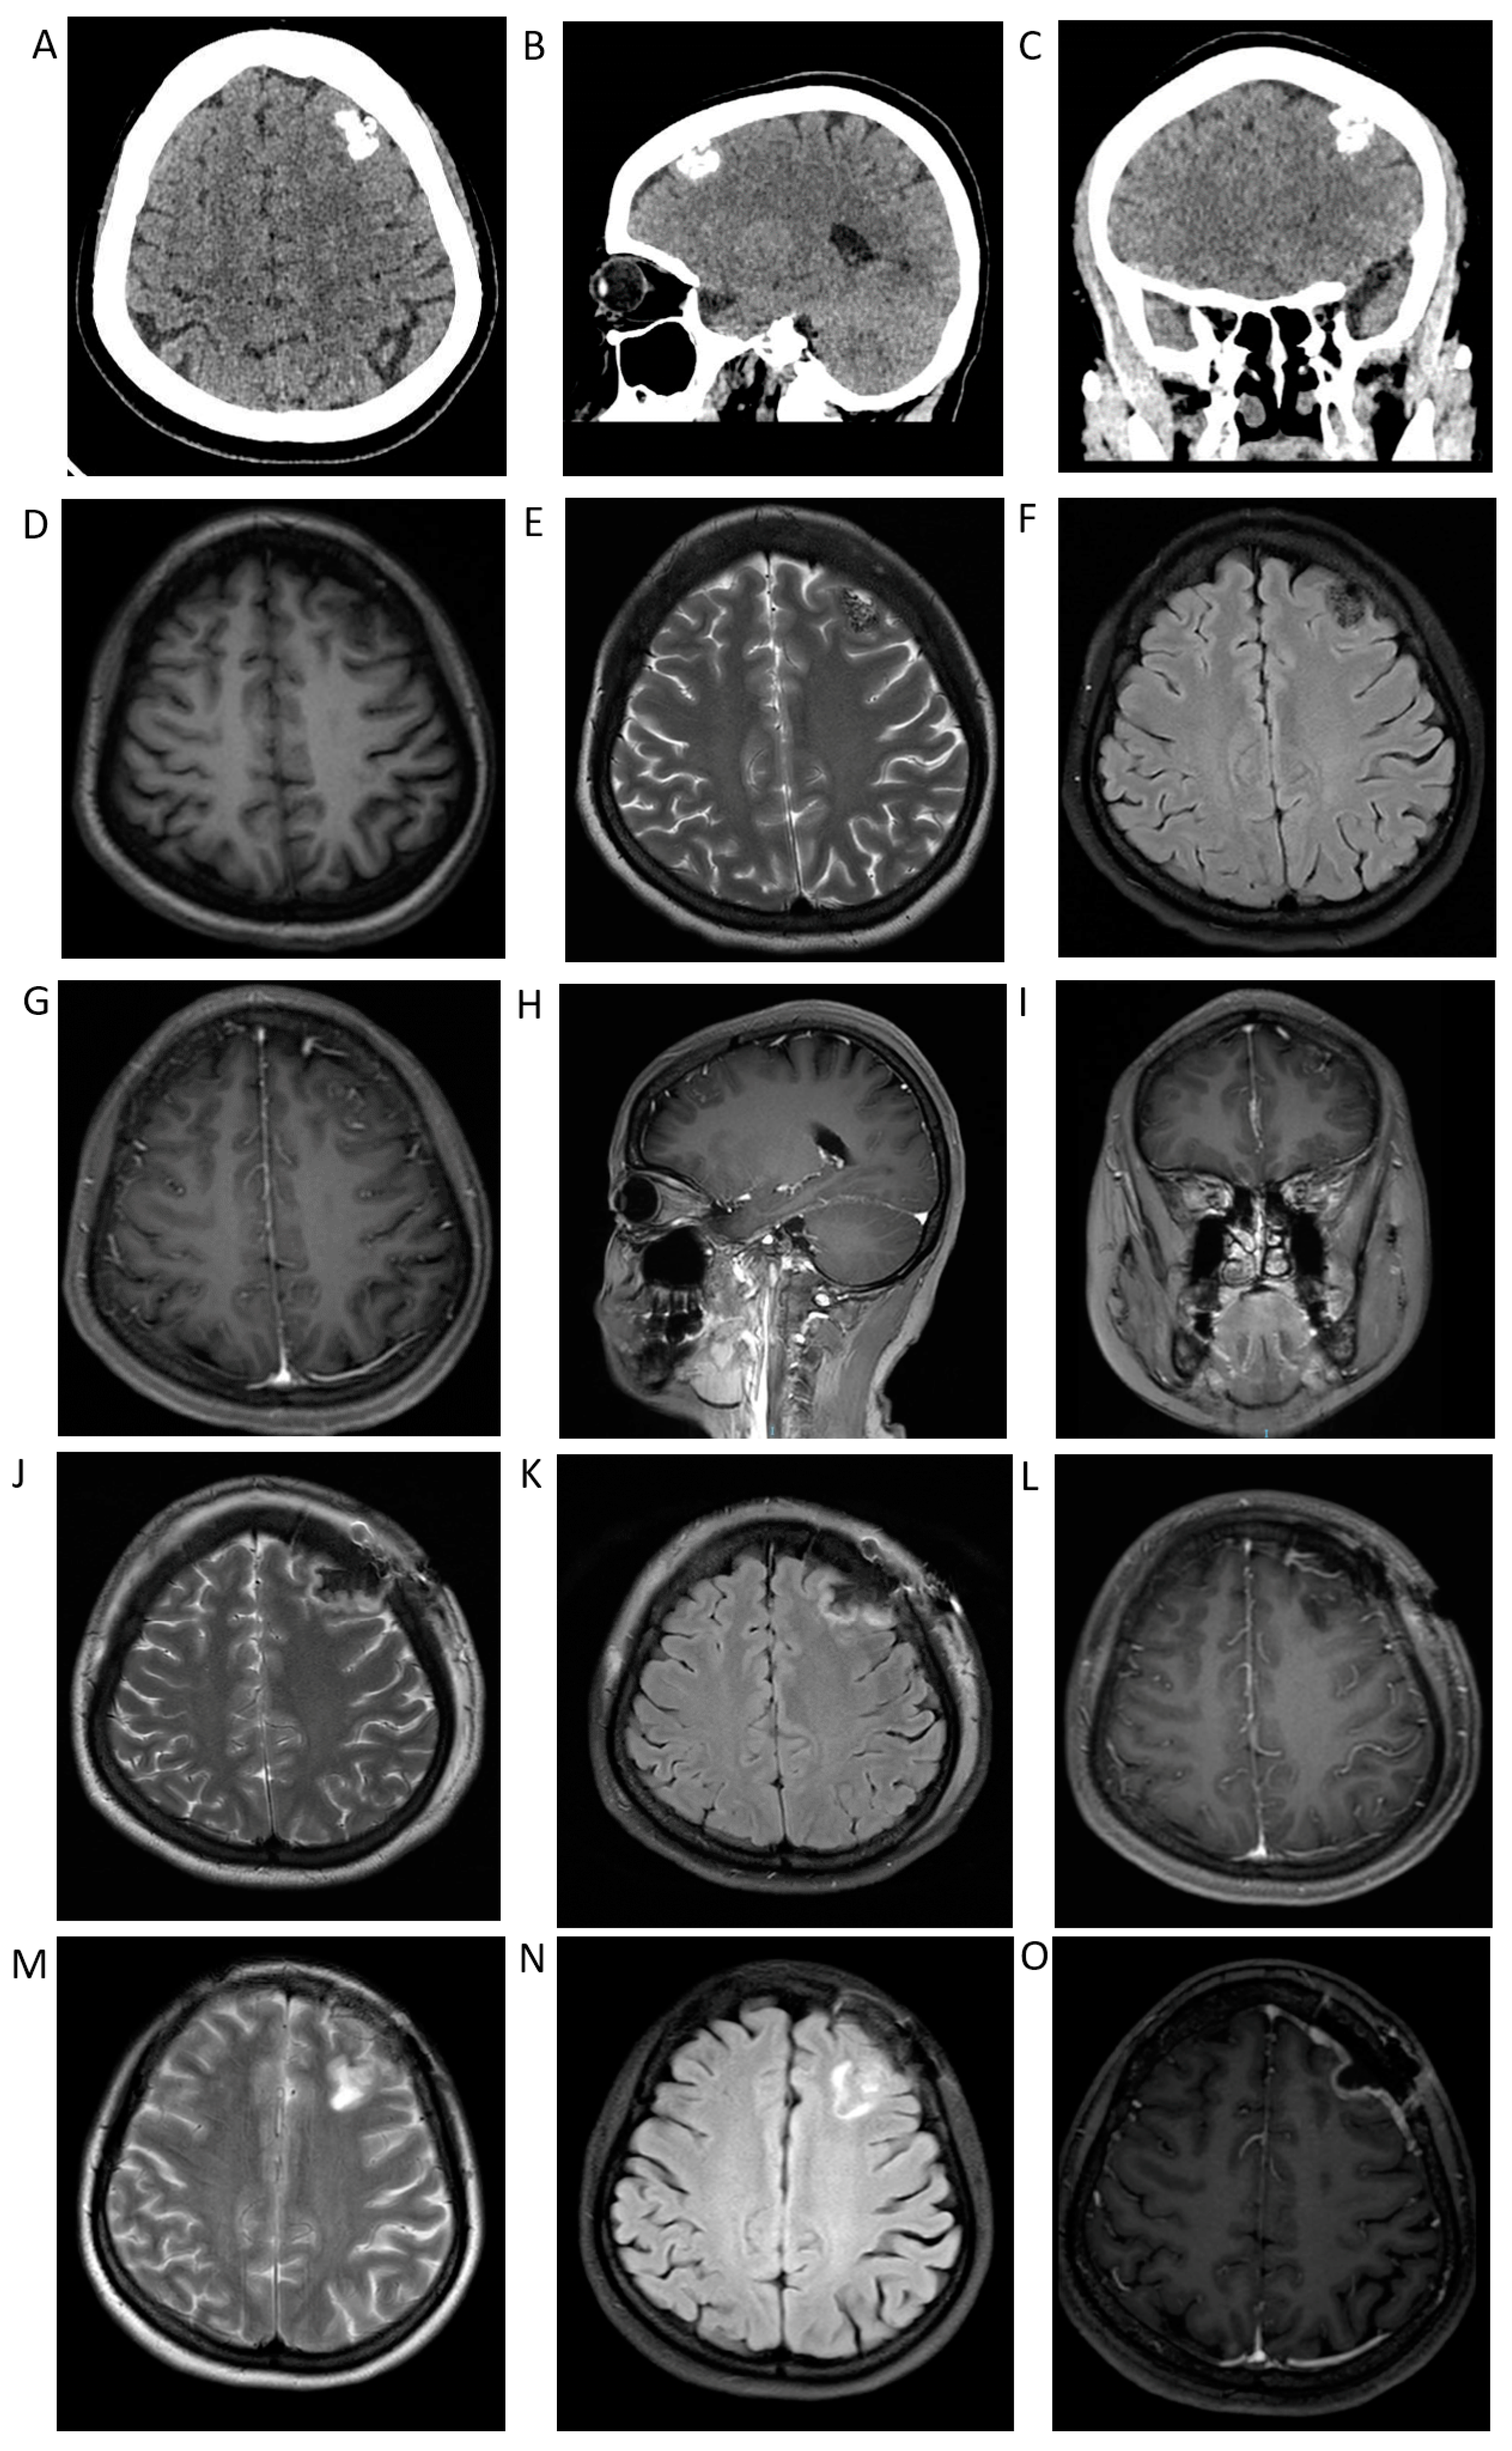

3. Case Presentation